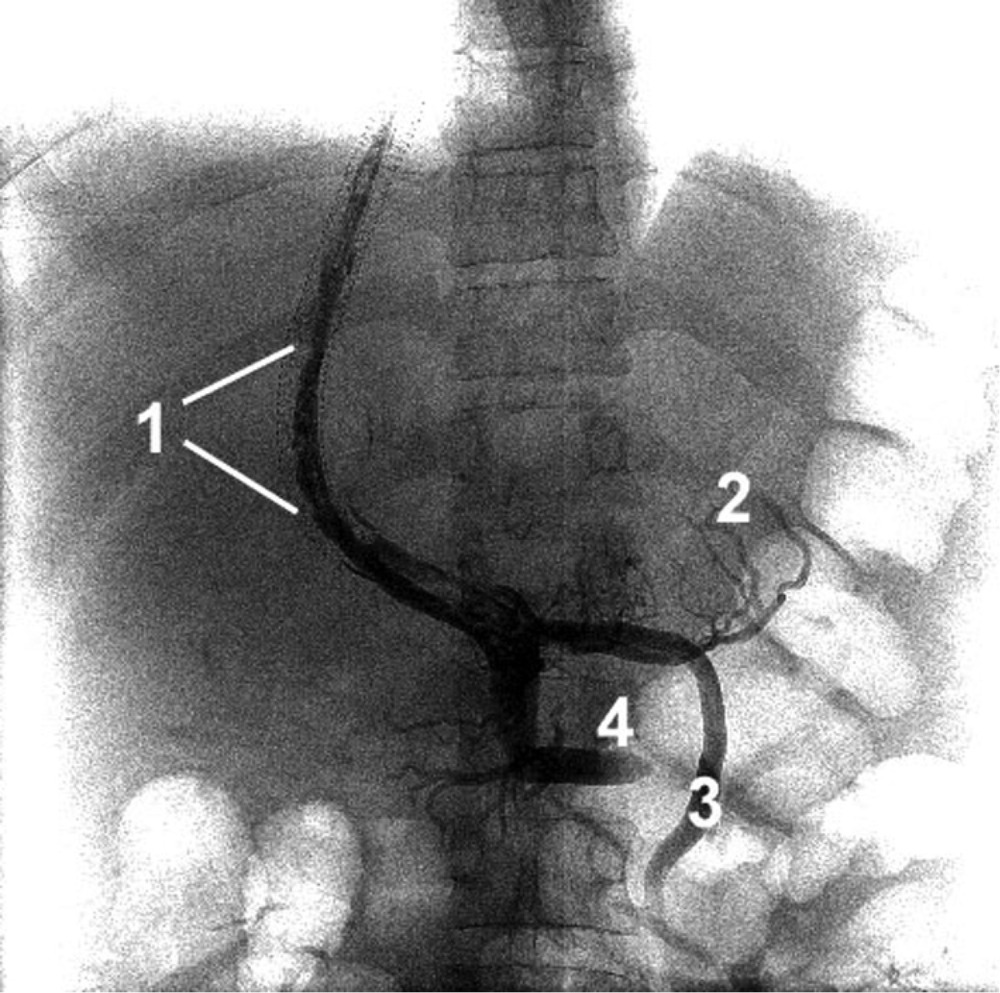

- Спленопортография. Инвазивное исследование сосудов бассейна воротной вены показано на этапе подготовки к хирургической коррекции заболевания. С помощью рентгеноконтрастного метода визуализируют все венозные сосуды и их коллатерали, выясняют размеры, протяженность и локализацию тромбоза.

Диагноз тромбоза селезеночной вены представляет большие трудности, причем отмечается наклонность к гипердиагностике этого процесса. С другой стороны, некоторые случаи тромбоза, особенно протекающие с кровотечениями, диагностируются как острая брюшная катастрофа и больные подвергаются операции, например в связи с подозрением на кровоточащую язву желудка. Поэтому необходим тщательный анализ анамнестических данных, пальпаторного обследования брюшной полости (наличие увеличенной селезенки), данных исследований крови (лейкопения, тромбоцитопения), прежде чем ставить диагноз тромбоза селезеночной вены. Очень часто тромбоз селезеночной вены сопровождается одновременно поражением воротной вены, в связи с чем диагноз тромбоза еще более усложняется. Все большее распространение получает метод контрастного изучения сосудов портальной системы (метод силенопортографии). Спленопортография заключается в чрескожном введении через иглу в пульпу селезенки контрастного вещества и производстве серийных снимков. Возможно применение и одномоментной спленопортографии, однако серийные исследования дают большее представление о состоянии портального Кровообращения и обладают большими диагностическими возможностями. Особенно показано применение этого метода при заболеваниях, сопровождающихся портальной гипертонией. Противопоказаниями для проведения этого метода исследования являются почечная недостаточность, геморрагические диатезы, острые заболевания печени.

После обычной подготовки больных для рентгенологического исследования органов брюшной полости и инъекции наркотика чрескожно вкалывают иглу в пульпу селезенки на 2—4 см после прокола капсулы и через нее вводят 70% кардиотраст, подогретый до 37—38°. На серийных снимках вначале определяется депо контраста в селезенке, вслед за чем начинают проявляться селезеночная, а затем воротная вена. При тромбофлебитической спленомегалии на спленопортограммах определяется депо контраста в селезенке, получить же изображение селезеночной и воротной вены не удается. Лишь иногда выявляется слабое заполнение контрастом коллатеральных сосудов с направлением от депо к верхнему полюсу селезенки и пищеводу.

Спленопортография является единственным методом, позволяющим достаточно точно диагностировать тромбоз селезеночной вены. Этот метод с успехом применяется и для диагностики тромбоза воротной вены. Изучение спленопортограмм позволило выделить два вида блоков в системе воротной вены—внепеченочный и внутрипеченочный, связанный обычно с развитием цирроза печени.